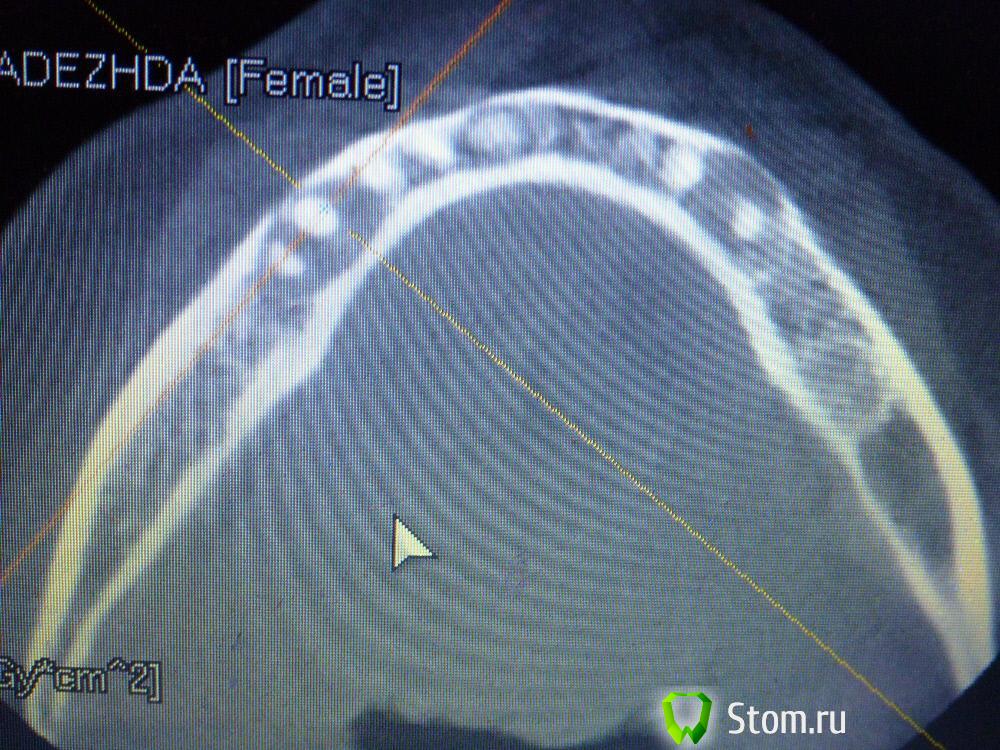

IvanK Опубликовано 25 ноября, 2011 Поделиться Опубликовано 25 ноября, 2011 Коллеги , посоветуйте Ваш план лечения.Пациентка обратилась с целью протезирования. Была направлена на ОПТГ. Обнаружены "кисты".Предположены амелобластома или первичная киста. Направлена на кафедру в 1 мед. Сказали, что "обычные кисты".Вижу 2 варианта:1). эндодонтическое лечение, цистэктомия, гистология, резекция верхушек корней, наблюдение, далее костная пластика?, имплантация. 2) Удаление зубов с периапикальными изменениями + 8-ка, гистология, пластика, имплантация боковых отделов. Ссылка на комментарий

IvanK Опубликовано 25 ноября, 2011 Автор Поделиться Опубликовано 25 ноября, 2011 Сразу прошу прощение за качество фотографий Ссылка на комментарий

Corvalus Опубликовано 26 ноября, 2011 Поделиться Опубликовано 26 ноября, 2011 Эндодонтическое лечение: 45,44,33-го тоже он в зоне кисты,34,36. Хуже дела обстоят с 35-м, глянуть бы прицельный снимок, если периапикальные изменения есть, то шуруп трудно достать будет. Обязательно реэндодонтия 43. Далее цистэктомия без всяких резекций с обязательной гистологией. Заполнять кисты не стал бы, достаточно крови, очаг гнойный. Через несколько недель парадонтологическое лечение, после костная пластика с отсроченной имплантацией. И в конце рациональное протезирование одиночными коронками. При нормальном эндодонтическом лечении рецедива кист не должно быть, а если и будет, то не на всех зубах сразу. Себе зубы удалять не стал бы, опыт лечения таких зубов есть, с имплантацией всегда решить можно по ходу поступления проблем. Второй вариант имеет место быть. Объяснить пациентке все за и против, пусть сама выбирает. Ссылка на комментарий